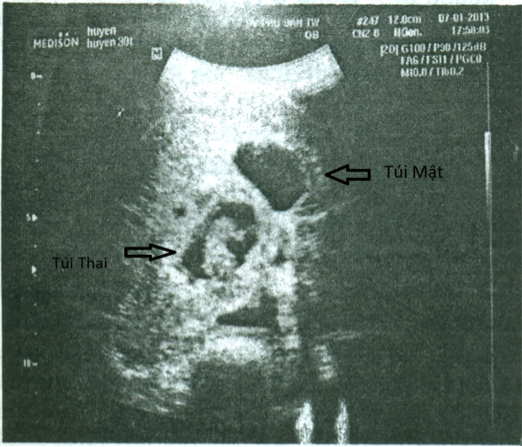

Bệnh nhân nữ 30 tuổi, PARA 1011, tiền sử mổ TNTC ở vòi tử cung bên phải; kinh nguyệt đều, vòng kinh 30 ngày. Bệnh nhân bị chậm kinh một tháng, đau âm ỉ hạ sườn phải 1 tháng, không ra máu âm đạo. Bệnh viện Phụ Sản Hà Nội nghi u nguyên bào nuôi và chuyển đến Bệnh viện Phụ Sản Trung ương. Xét nghiệm β-hCG: 73.047 IU/L; siêu âm Doppler: dưới gan có hình ảnh túi thai d=35mm, chiều dài phôi: 22mm, tim thai (+). Chẩn đoán thai dưới gan. Nội soi: khối thai 3cm nằm ở cạnh phải túi mật, gần tĩnh mạch cửa. Bóc khối thai và cầm máu bằng dao điện và chèn Spongel. Xét nghiệm β-hCG sau 72 giờ: 14.109 IU/L. Giải phẫu bệnh: gai nhau điển hình.

| Hình 3. Hình ảnh siêu âm của bệnh án 2 |